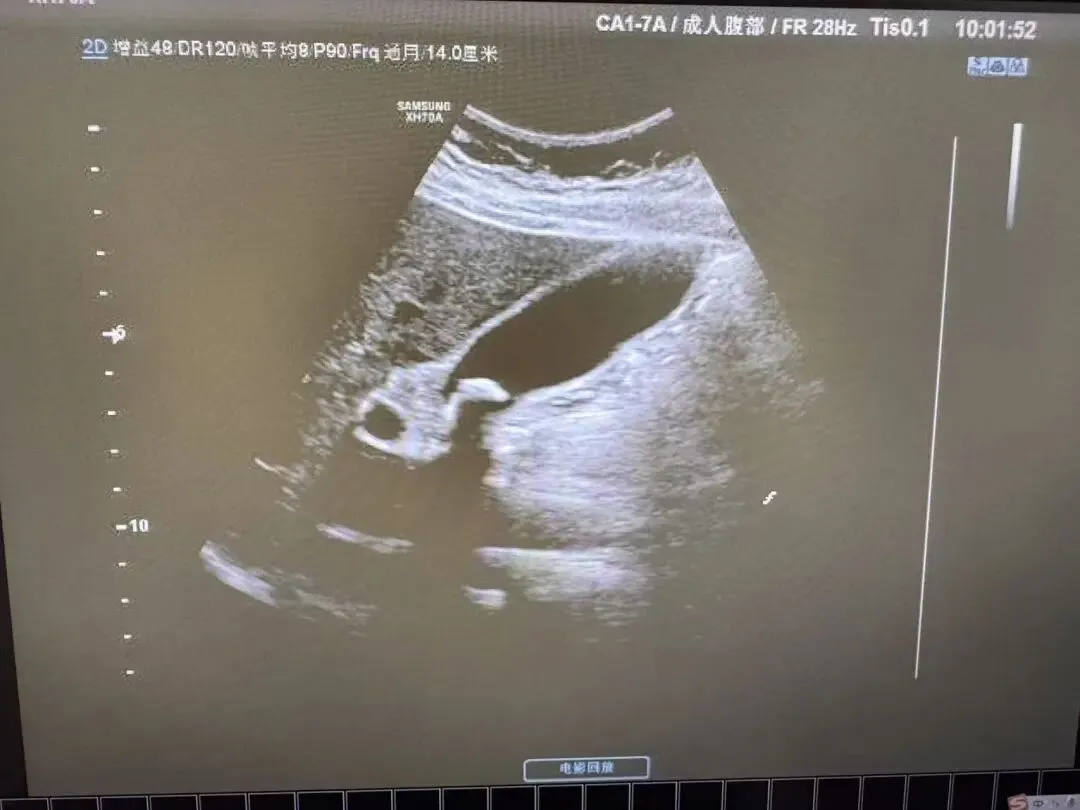

胆囊颈部结石

胆囊颈部强回声,后方伴声影,胆囊内充满稀疏的细小光点。